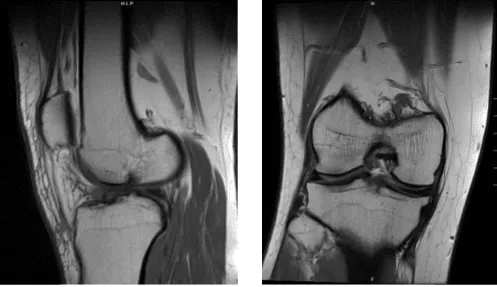

The patient is a 34 year-old male seen in the office multiple times in the past. He has had pain in the right knee on the inner side, which has not been relieved with nonoperative treatment in the form of physical therapy, chiropractics, and antiinflammatory medications. MRI was done.

MRI were reviewed and discussed; the Linear signal elevation is identified within the posterior hom of the medial meniscus on coronal sequence image #12 and sagittal sequence image #26 associated with intrasubstance tears. Tear within the lateral meniscus is not appreciated.

Preservation of joint space height is noted in both medial and lateral femorotibial compartments. Intermediate signal intensity is noted in association with the anterior cruciate ligament suggestive of sprain.

There is no evidence of discontinuity or retraction of the posterior cruciate ligament to indicate tear. There is no evidence of tear of the medial collateral ligament. There is no evidence of tearing of the lateral collateral ligament.

There is no evidence of tearing of the quadriceps tendon. There is no evidence of tearing of the patellar tendon. There is no evidence of tear of the medial or lateral patellar retinaculum. Popliteus peritendinous fluid associated with tenosynovitis.

Semimembranosus and semitendinosus peritendinous fluid is also associated with tenosynovitis. There is no evidence of signal changes associated with the iliotibial band. There is no evidence of degenerative changes of the proximal tibiofemoral articulation.

Mild joint effusion is noted with both suprapatellar and infrapatellar components. There is no evidence of Baker’s cyst posterior to the medial femoral condyle. There is no evidence of chondromalacia within the posterior patella.

Tibial tubercle to trochlear groove distance measures approximately 5 mm within normal limits. Trace anterior soft tissue edema is noted. There is no evidence of bone marrow signal change to indicate fracture, avascular necrosis, osteomyelitis or bone marrow replacement process.

Impression: Intrasubstance tear posterior horn of the medial meniscus. Anterior cruciate ligament sprain. Popliteus, semimembranosus, and semitendinosus tenosynovitis and mild effusion. Which means that the MRI results showed medial meniscus tear and tearing of the ACL.

Magnetic resonance imaging scan of the right knee